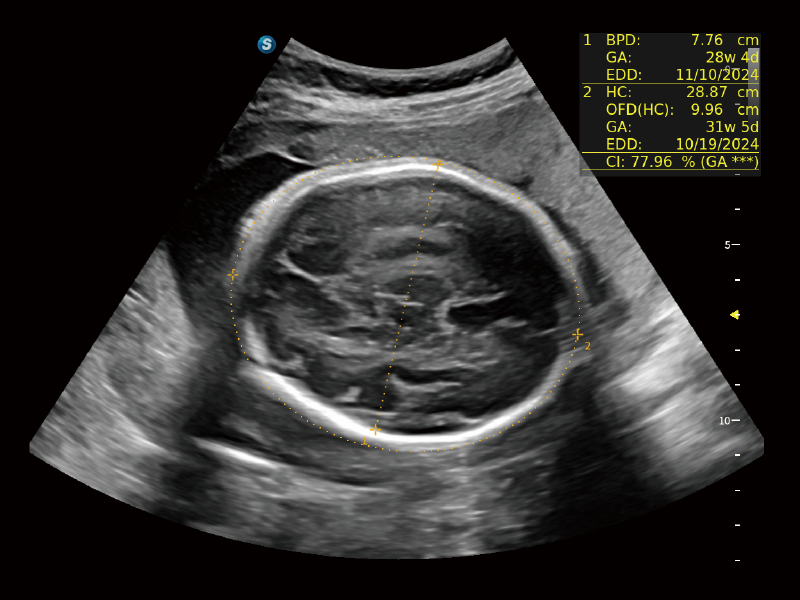

作为开立医疗全新打造的超高端旗舰超声产品,从探头抬起唤醒开启扫查到多维探头发射接收,通过先进的场成像发射、自适应聚合重建等技术,基于RF Data原始射频数据在图像生成、高端功能等方面实现突破,为妇产科、儿科提供全方位临床解决方案。

独有场成像发射技术

自适应聚合重建技术